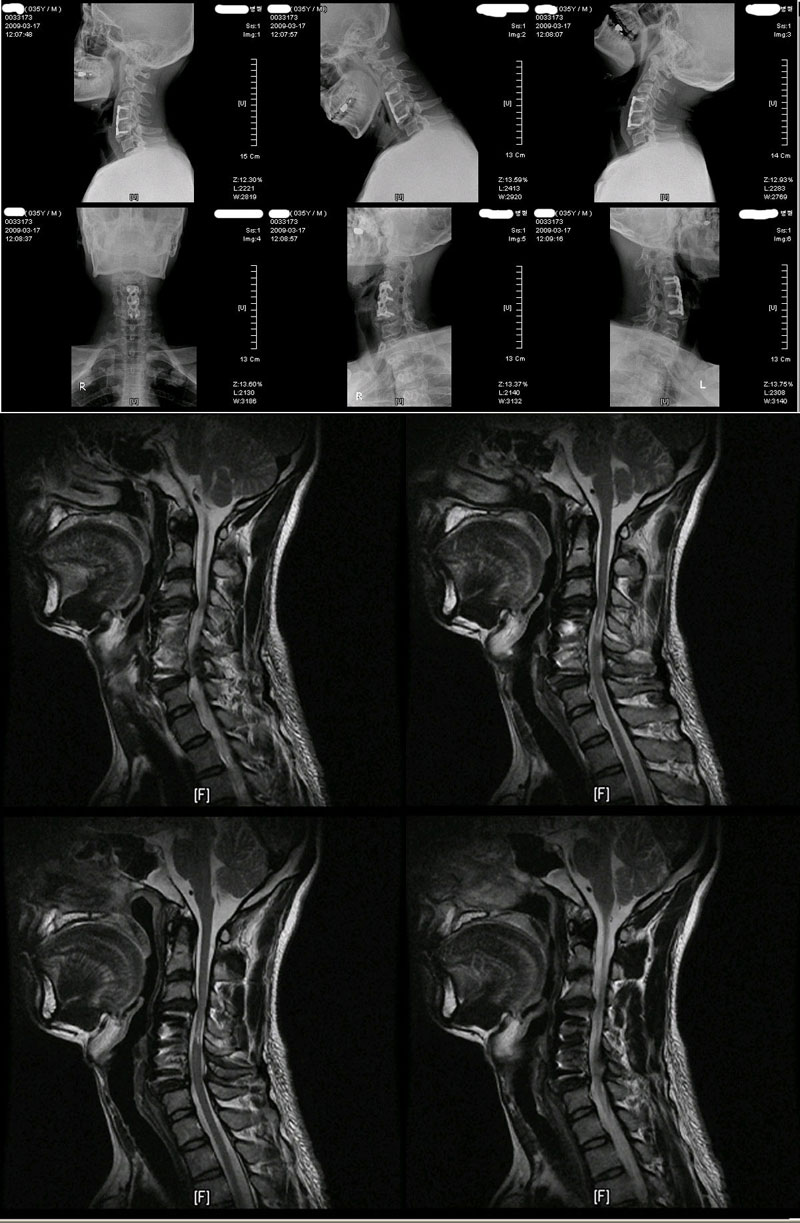

---------------------- Ʒ ũ 2ȸϰ mri ÷ Դϴ. ù ȸ ȭ ϸ鼭 űϰ Ͽϴ. ũ ε ϸ鼭 ° 㸮 ᵵ µ ȸ ϴ ð ~~ 㿡 ¥ ¥ űϰ ѹ ʰ ٴ Դϴ,.. ⸸ ڽϴ. ֽ ȸ 帮 ֽ е մϴ.. Ͽ ũ 㸮 ġDZ Ұ̸ ı ÷ 帮 Ҳ... ---------------------- Ű 176 69 36 ()ijħ ڸǥغ ǥغ ˰Ե ͳ ˻ڷ õ ()ijħ ڸǥغ ǥغ ϱ ȣϽ 6C.ڸ 6C. κ 6C.ھ Ḳ 6C.ڻ 6C.7C.ھ հ ̳ 7C.ڿʰ 1T.ڼյ չٴ 1T.ڼո 1T.ڼհ ü ̳ 1T. κ 4L.ھƷ 4L°Ű, 4L.°Ű̻ 4L.ڿ, 4L.ڵ Ʒ 5L.ڴٸ Ʒκ̳ 5L.ڹ߸̳ 5L.ڹ߹ٴ̳ ߵ ̳ ȭŸ̳ 5L.ڹ߰ ̳ ȭŸ̳ 5L.Ƹ 㰡 õ().° ̳ õ().ھ ()ũ( ߰Ż) ,㸮ũ ߵũ,߰ Ը Ͽ ũ(߰Ż)ġ, հ , ġ, , Ḳ ġ 㸮ũ(߰Ż) ߿ ġ , 㸮 ̳ ġ ٸ ġ ߰ ġ ()ijħ ڸǥغ ǥغ ϰ ߴ ġ ũ 2004 9 4-5,5-6 1. 2009 4 3-4 ũ 2 㸮ũ ٸ ߰ ߹ٴ - |